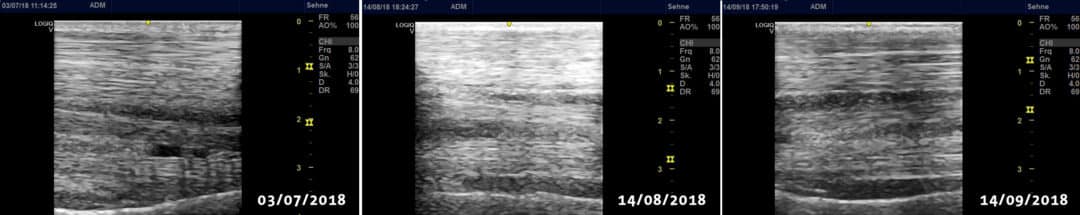

The injured tendon was treated locally with the pulsed diode therapy laser . The progress of the treatment was monitored using RAC pulse diagnostics, which can also be carried out with the therapy laser. Pulse control showed increasing improvement, which was confirmed by a further ultrasound examination after four weeks of laser therapy . Hardly any traces of the tendon injury were visible on the ultrasound images.